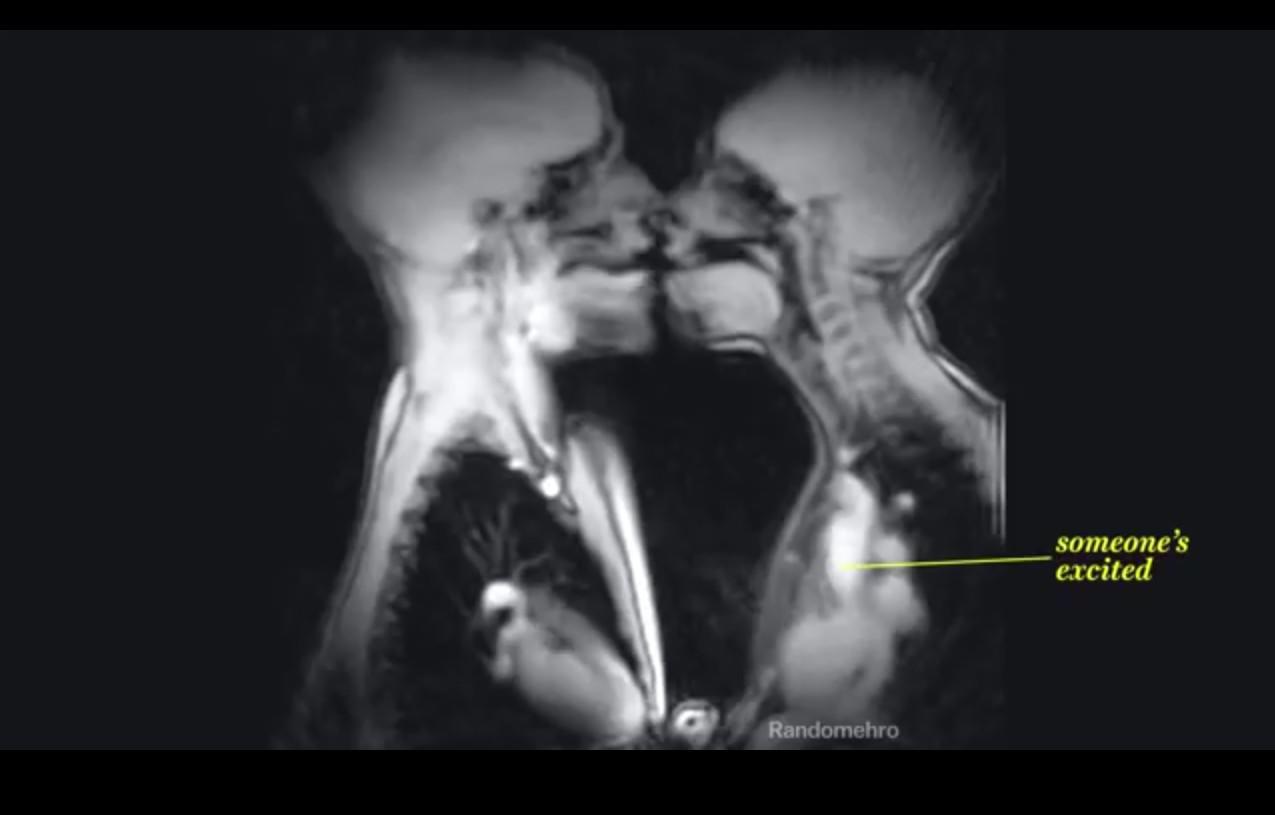

Le site internet VOX propose une vidéo de volontaires faisant plusieurs actions de la vie courante, alors qu'ils sont vus par IRM.

Avez-vous déjà vu la réaction du corps quand deux personnes s'embrassent ? C'est maintenant possible grâce à la vidéo du site internet VOX qui montre des personnes filmées via imagerie par résonance magnétique (IRM) ."Cette technique permet de voir à l'intérieur du corps en repérant la position des eaux moléculaires de l'organisme" expliquent les auteurs des images. Ce procédé étant moins invasif que les rayons X, les scientifiques ont pu filmer les volontaires plus longtemps que lors d'une simple radio.

Dans cette vidéo on voit le mouvement de la langue quand on parle, le jus de fruits couler dans la gorge ou encore l'intérieur du vagin pendant la pénétration sexuel. Plus impressionnant, la vidéo montre l'intérieur de l'utérus d'une femme pendant l'accouchement.